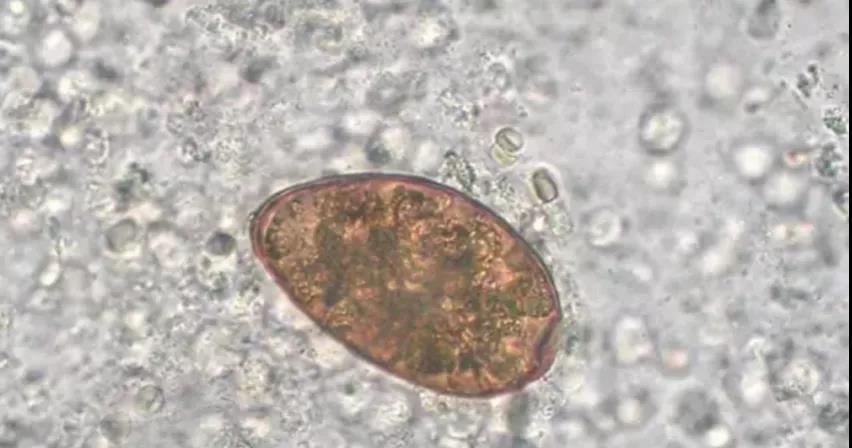

痰液中的肺吸虫卵

肺吸虫顾名思义,是因为幼虫或成虫会寄生在人或哺乳动物的肺脏内而得名。虫卵在淡水螺内发育成尾蚴,在淡水蟹、蝲蛄(淡水龙虾)等动物体内发育成囊蚴。囊蚴侵入到人体后慢慢发育为成虫。